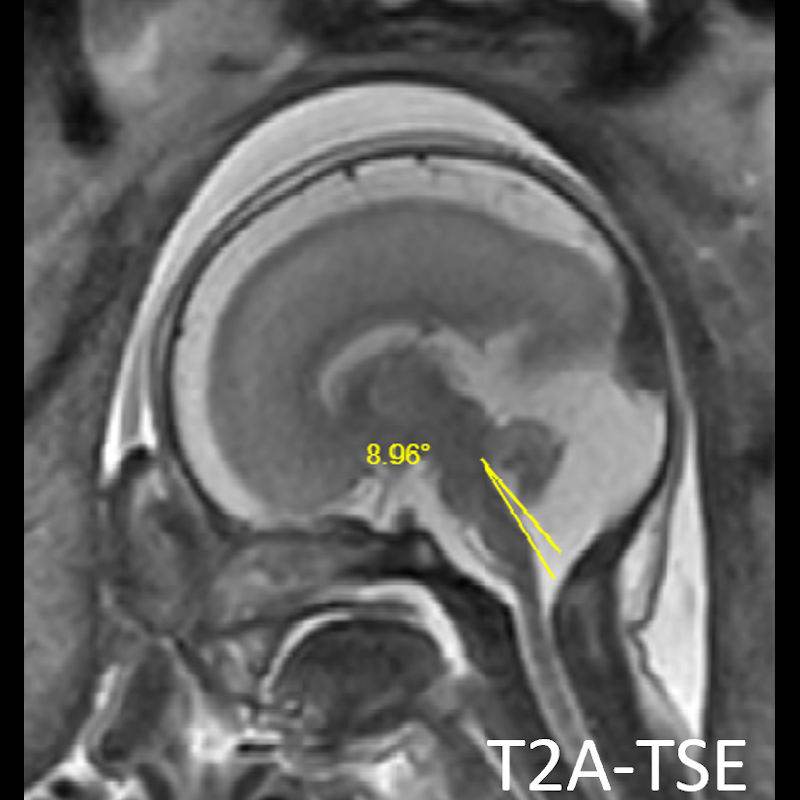

- A) USG incelemede serebral kortikal yapılar düzleşmiş (ok), gyrus sayısı azalmıştır (ok). Kalın ve ekojenik korteks mevcut olup korteks -beyaz cevher ayrımı silik görünümdedir. Posterior fossada ekstraaksiyel BOS mesafesi artmış görünümdedir (ok).

- B) Aksiyel ve sagittal T2A görüntülerde gyrus ve sulkuslarda azalma mevcut olup korteks kalınlaşmış görünümde ve operkulizasyon ayırt edilememiştir. Korteks beyaz cevher ayrımı zor seçilmektedir (ok) Ekstraaksiyel BOS mesafesi artmış görünümdedir (ok). Yapılan ölçümlerde; tegmentovermian açı :8 derece (ok) serebellar vermis boyutları kraniokaudal: 16 mm, aksiyel: 5,5×8,5 mm (ok) ölçülmüş olup BPD:27w ile uyumlu olan fetüste haftasıyla uygun olarak değerlendirilmiştir.

- Lizensefalili olgularda MRG’de beyin korteks yüzeyi düz ve belirgin kalındır. Bazı olgularda orbito-frontal ve inferior temporal bölgelerde gyrus yapıları gelişmiş olabilir.

- Gri/beyaz cevher oranı beyaz cevher aleyhine azalmıştır.

- Operkulizasyon yokluğuna bağlı sylvian fissürün açık görünümü ve vertikal yerleşimi karakteristik bir bulgudur. Serebral yapılar; sığ ve vertikal yerleşimli sylvian fissür sebebiyle “8” görünümündedir. Ancak bu görünümün 26. gestasyonel haftaya kadar normal olduğu akılda tutulmalıdır.

- İnsula açıkta olup klastrum ve eksternal kapsül bulunmayabilir. Beynin gross görünümü fetüste sulkusların oluşmaya başladığı 20. gestasyonel haftayla benzer görünümdedir.